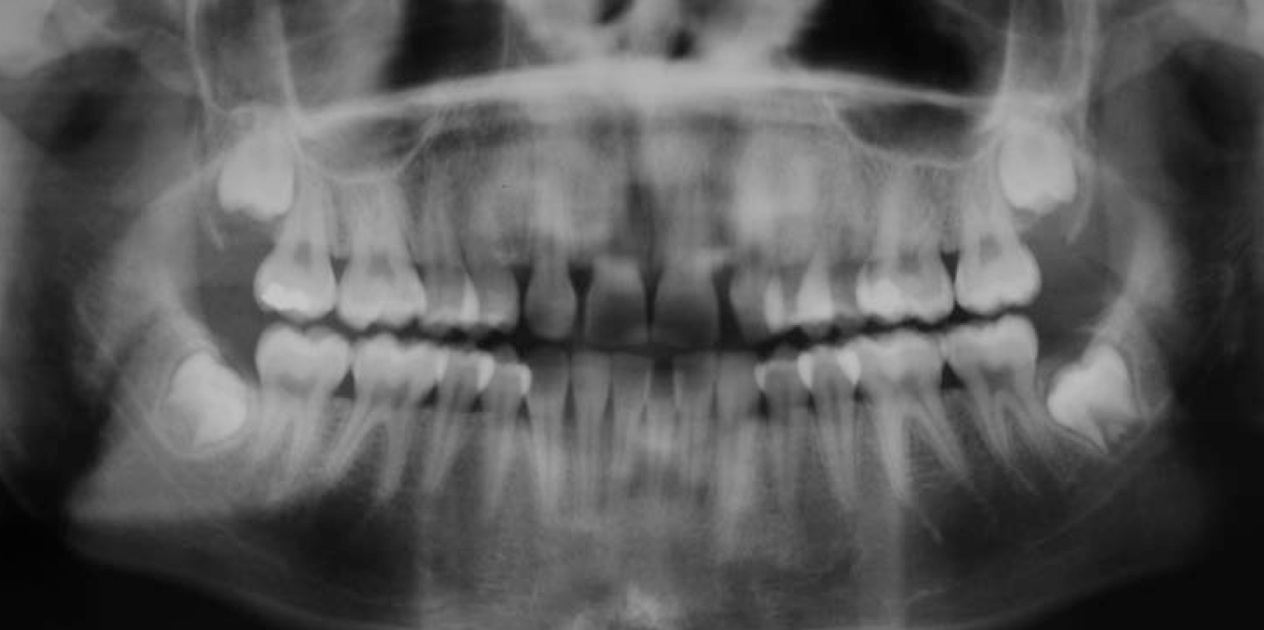

Based on this xray, what developmental and congenital abnormality is observed?

a. number of teeth

b. size of teeth

c. eruption of teeth

d. morphology of teeth